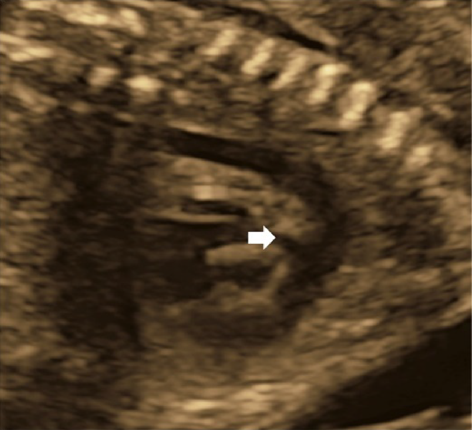

It is up to the types of fetal tachycardia whether heart failure develops, whether arrhythmias diagnosed are lethal, and whether in-utero treatment turns out effective. Multiple factors must be taken into consideration when planning treatment and management.197)

3. Fetal Hydrops

Signs of fetal hydrops, progressive cardiomegaly, and AV valve regurgitation indicate that tachycardia-induced collapse is imminent and that the time available for in-utero treatment is limited. The mortality rate for fetuses with hydrops (12–35%) is higher than that of fetuses without hydrops (0–4%). Once fetal treatment solves tachycardia, hydropic features improve drastically. Fetal death is uncommon within the initial fortnight after starting in-utero treatment for tachycardia, as cardiac rhythm becomes better with effective fetal treatment, even in patients whose hydrops has progressed by the time of diagnosis.191, 198, 199) Early delivery employed in patients with hydrops secondary to tachycardia would produce a worse prognosis due to complications associated with the prematurity of the infant. Several reports recommend intrauterine therapy including digoxin and a second-line drug as the initial treatment in fetuses in whom hydrops has already manifested its symptoms.189, 193)